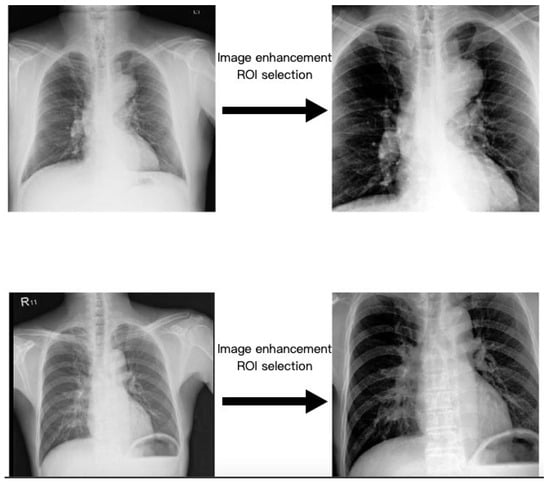

2.3. Region of Interest

2.4. Image Enhancement